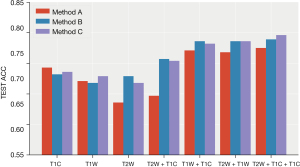

- Plan B (I + III): (see Table 3, Figure 7)

The prediction performances of all models in plan B (95% confidence interval)Model Performance T2W T2W + T1C T1W + T1C T2W + T1W T2W + T1W + T1C Logistic ACC 0.571 (0.509, 0.634) 0.654 (0.608, 0.699) 0.668 (0.619, 0.716) 0.707 (0.658, 0.757) 0.711 (0.672, 0.749) AUC 0.576 (0.501, 0.65) 0.671 (0.596, 0.747) 0.684 (0.629, 0.738) 0.756 (0.709, 0.804) 0.713 (0.648, 0.778) KNN ACC 0.6 (0.538, 0.662) 0.557 (0.506, 0.608) 0.65 (0.591, 0.709) 0.607 (0.561, 0.653) 0.582 (0.518, 0.646) AUC 0.58 (0.515, 0.644) 0.543 (0.479, 0.606) 0.581 (0.509, 0.652) 0.605 (0.552, 0.657) 0.574 (0.496, 0.652) RF ACC 0.732 (0.699, 0.765) 0.705 (0.659, 0.752) 0.748 (0.721, 0.776) 0.782 (0.741, 0.823) 0.773 (0.718, 0.828) AUC 0.642 (0.583, 0.702) 0.62 (0.567, 0.672) 0.654 (0.577, 0.731) 0.733 (0.667, 0.799) 0.668 (0.59, 0.746) Vote ACC 0.732 (0.709, 0.756) 0.757 (0.721, 0.793) 0.786 (0.766, 0.806) 0.786 (0.758, 0.814) 0.789 (0.763, 0.816) AUC 0.639 (0.585, 0.692) 0.61 (0.554, 0.665) 0.649 (0.57, 0.728) 0.717 (0.657, 0.777) 0.659 (0.583, 0.735) ACC, accuracy; AUC, area under curve.

The classification model integrated by two strong classifiers showed the best performance, reaching the highest average accuracy rate of 0.789 (0.763, 0.816) and AUC of 0.659 (0.583, 0.735) on the T2W + T1W + T1WC sequence. Performance was relatively stable, and the accuracy rate was higher than 70% in the seven sequence combinations. Following a RF, the average accuracy rate reached 0.782 (0.741, 0.823), and the AUC reached 0.733 (0.667, 0.799) in the T2W + T1W sequence. The results of the nearest neighbor and logistic regression models are not ideal, especially the nearest neighbor algorithm.

- Plan C (I + II + III): (see Table 4, Figure 8)

The prediction performances of all models in plan C (95% confidence interval)Model Performance T2W T2W + T1C T1W + T1C T2W + T1W T2W + T1W + T1C Logistic ACC 0.593 (0.528, 0.658) 0.646 (0.602, 0.691) 0.696 (0.633, 0.76) 0.707 (0.666, 0.748) 0.7 (0.664, 0.736) AUC 0.576 (0.512, 0.641) 0.671 (0.607, 0.735) 0.681 (0.636, 0.726) 0.737 (0.677, 0.798) 0.731 (0.661, 0.801) KNN ACC 0.589 (0.529, 0.65) 0.532 (0.477, 0.587) 0.664 (0.618, 0.71) 0.632 (0.594, 0.67) 0.596 (0.538, 0.655) AUC 0.56 (0.499, 0.62) 0.544 (0.501, 0.587) 0.624 (0.557, 0.69) 0.612 (0.56, 0.664) 0.579 (0.508, 0.65) RF ACC 0.725 (0.686, 0.764) 0.709 (0.676, 0.742) 0.725 (0.693, 0.757) 0.77 (0.732, 0.807) 0.771 (0.727, 0.816) AUC 0.648 (0.594, 0.703) 0.63 (0.565, 0.695) 0.658 (0.576, 0.74) 0.71 (0.638, 0.782) 0.697 (0.614, 0.78) Vote ACC 0.736 (0.705, 0.766) 0.754 (0.72, 0.787) 0.782 (0.761, 0.803) 0.786 (0.753, 0.818) 0.796 (0.76, 0.833) AUC 0.636 (0.585, 0.688) 0.622 (0.559, 0.686) 0.661 (0.571, 0.75) 0.704 (0.632, 0.777) 0.689 (0.615, 0.763) ACC, accuracy; AUC, area under curve.

After combining the key features of the different sequences, the performance of the three sequences was greatly improved in the integrated classification model [ACC: 0.796 (0.76, 0.833), AUC: 0.689 (0.615, 0.763)]. The average accuracy rate was close to 80%, and the average AUC exceeded 70%. Furthermore, the performance was stable, and the accuracy rate was higher than 70% in multiple sequence combinations.

After the combination of features, the performance of the other models improved to varying degrees. The average accuracy of the RF was 0.771 (0.727, 0.816), and the AUC was 0.697 (0.614, 0.78).

After combining the key characteristics of the different sequences, the combined effect of the three sequences was greatly enhanced in the ensemble model [ACC: 0.796 (0.76, 0.833), AUC: 0.689 (0.615, 0.763)]. The average accuracy rate was close to 80%, and the average AUC exceeded 70% (Figures 9,10).

After analyzing the commonly used classifiers for brain tumors (25,26), we chose five models for classification: logistic regression (logistic), RF, KNN, SVM, and a soft voting integrated model (RF, SVM). The integrated classification model based on RF and SVM had the best predictive performance, which could be due to the combination of the advantages of the two models. In our research, T2W had the highest performance in predicting the expression level of Ki-67 in all sequences, and the acquired image features had a unique degree. The accuracy of the T1W sequence was slightly worse than that of the T2W sequence. In addition, we did not just identify a single sequence to predict the patient’s Ki-67, but also performed seven combinations of three sets of sequences.

We used selected combinations of the most valuable features selected from the different sequences to screen out the more meaningful features to predict Ki-67 expression levels. After the sequences were combined, the prediction performance of the five models was improved to varying degrees. The performance improvement in the logistic regression was particularly obvious. The image features of the different sequences could reflect the expression level of Ki-67, and we could superimpose the features of the different sequences to increase the level of discrimination.

The C plan U-test + RF + LASSO was relatively less used among the three combination schemes in other studies. In our research, the C scheme was more robust and had the highest performance. This finding might be because after adding the linear method (LASSO) and the nonlinear method (RF), the interference of irrelevant variables was eliminated from both angles simultaneously, making its efficiency the highest. This discovery also provided new ideas for subsequent related research.

Although KNN had some improvement after multi-sequence merging, it was still the worst of the models. SVM (RBF) and RF had relatively better effects, and the integrated model was the best. After combining multiple sequences, the effect of logistic regression was greatly improved, indicating that when the key information of the sample was sufficient, some simple linear classification models could also obtain better results.